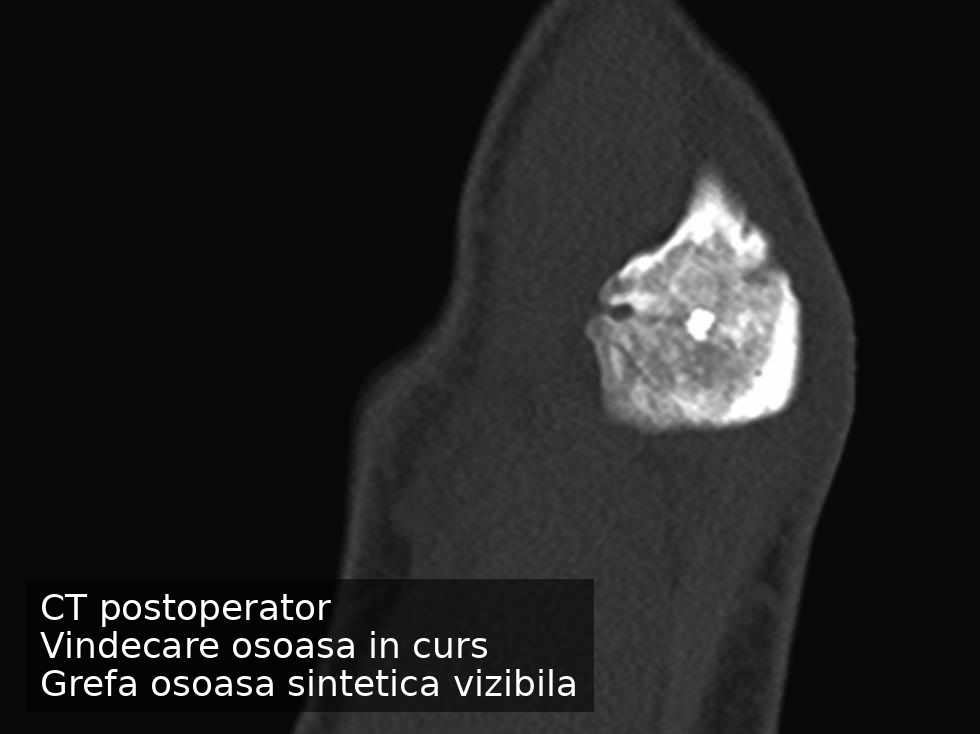

Am ales o soluție de fixare fără material metalic permanent, asociată cu augmentare osoasă, care să ofere stabilitate suficientă pentru vindecare, respectând în același timp biologia osului. Decizia a fost luată în urma unei discuții detaliate cu pacientul, în care obiectivul principal a fost revenirea la activitatea sportivă fără a compromite funcția cotului pe termen lung.

Evoluția postoperatorie a fost favorabilă, cu reluarea progresivă a activității și consolidare osoasă în curs. Revenirea în competiție a fost mai rapidă decât intervalele raportate frecvent pentru situații similare, fără a fi necesară o reintervenție. Vindecarea este încă în desfășurare, având în vedere deficitul osos inițial, însă obiectivele funcționale stabilite au fost atinse.